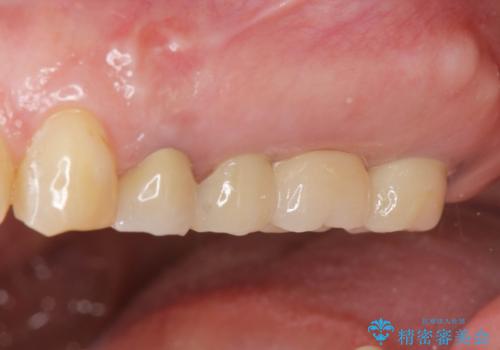

治療後、しっかりと咬合機能が回復され見た目の自然さにも満足いただくことができました。